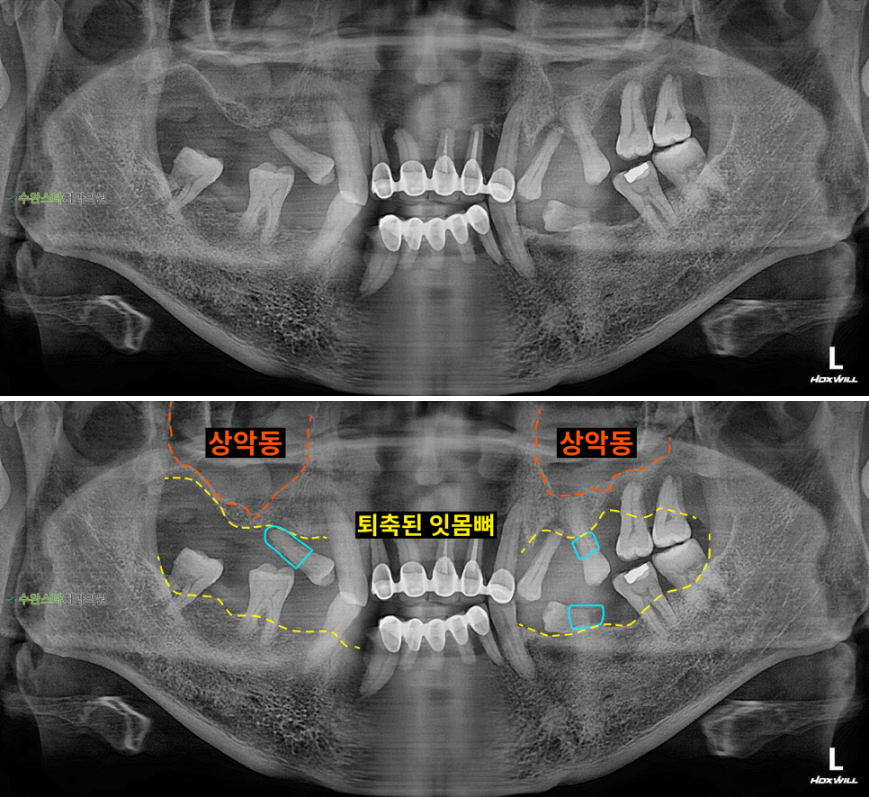

처음 내원 시 파노라마, 50대 남성 (2026. 1 촬영)

내원 시 파노라마 사진입니다.

잇몸뼈가 전체적으로

모두 많이 퇴축된 상태라

발치 후 뼈 이식을 동반한

임플란트가 필요한데요.

잇몸뼈가 부족한 경우에는

상악동 거상술을 통한

전체적으로 뼈이식이 필요합니다.